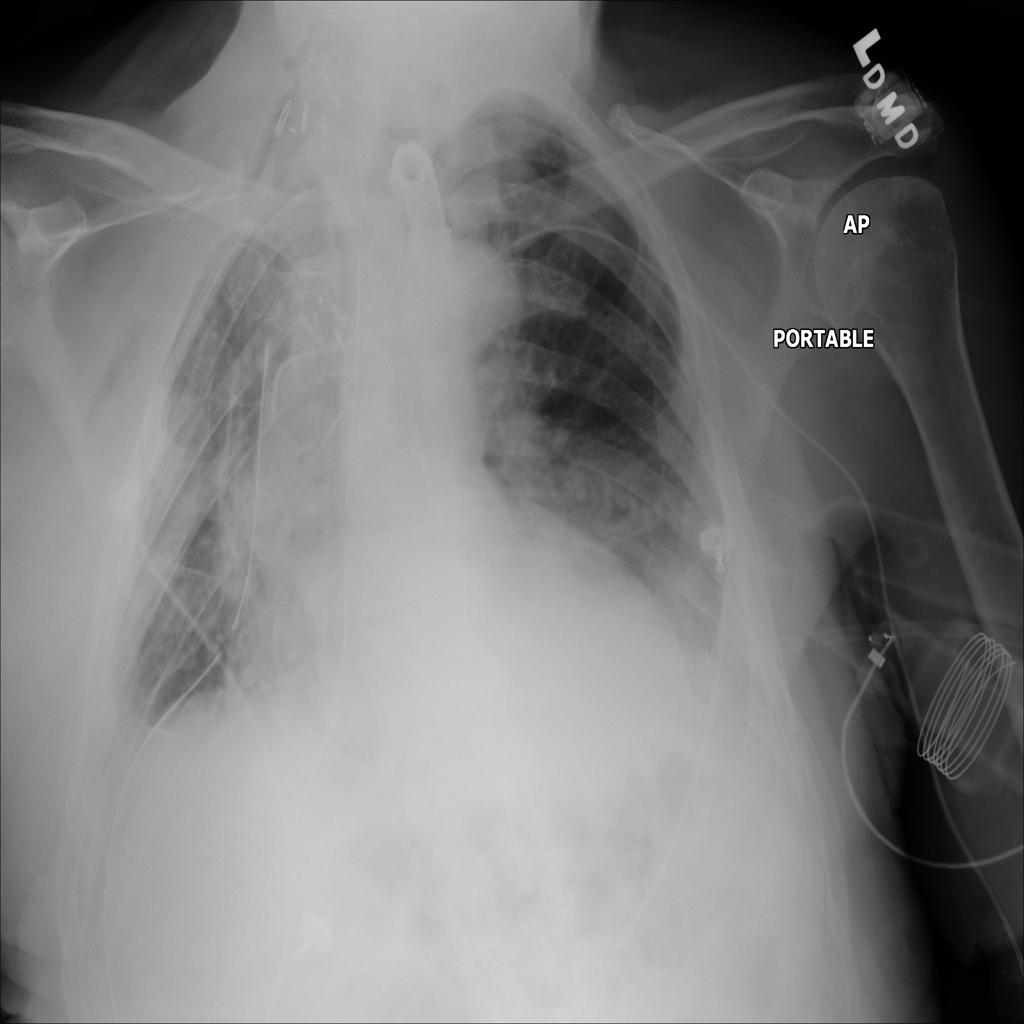

PAT-D041 · IMG-000Atelectasis

PAT-D041 · IMG-000

PA

PAT-D041 · IMG-001Atelectasis

PAT-D041 · IMG-001